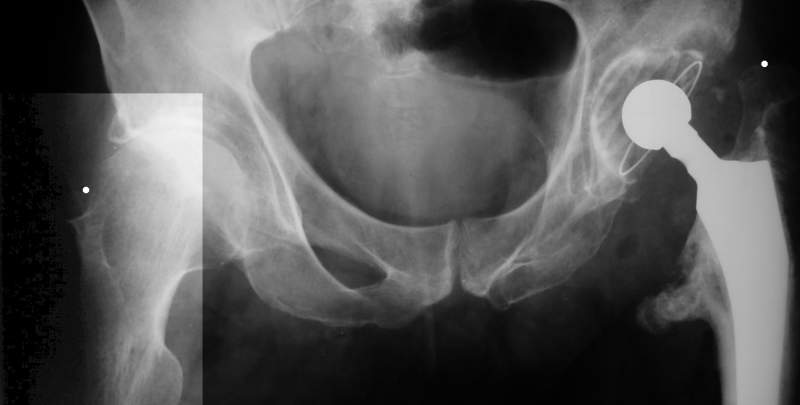

Больного прооперировали на прошлой неделе (цементный протез, цемент с

гентамицином). Использовали задне-боковой доступ. В области перелома

подвижности практически не было, так что тему сообщения уместно

заменить на "неправильно сросшаяся шейка". И в головке, и во впадине

были значительные дегенеративные изменения, так что ни биполяр, ни

остеосинтез тут неуместны (хотя это предлагали в ortopod'е). После

релиза удлинили ногу на 3 см. Дальше удлинять побоялись из-за

натяжения седалищного нерва, хотя в принципе можно было бы еще 15-20

мм нарастить. По послеоперационной рентгенограмме анатомическое

укорочение порядка 15 мм. Клинически при ходьбе - 4 см, но это за счет

перекоса таза.